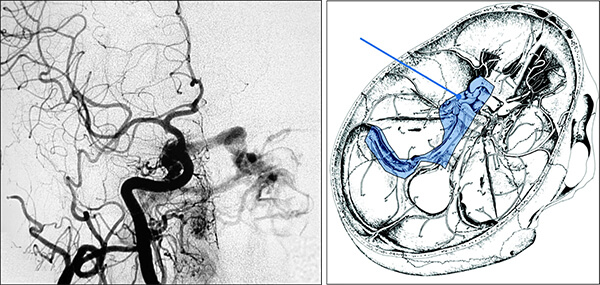

Η αξονική αγγειογραφία έχει ελαττωμένη ευαισθησία έναντι της μαγνητικής αγγειογραφίας.

Παρ´ όλα αυτά η συμβατική ενδαρτηριακή αγγειογραφία είναι η πιό ακριβής γιά την αναγνώριση αλλά και την κατηγοριοποίηση των ΑΦΔ της σκληράς μήνιγγας.